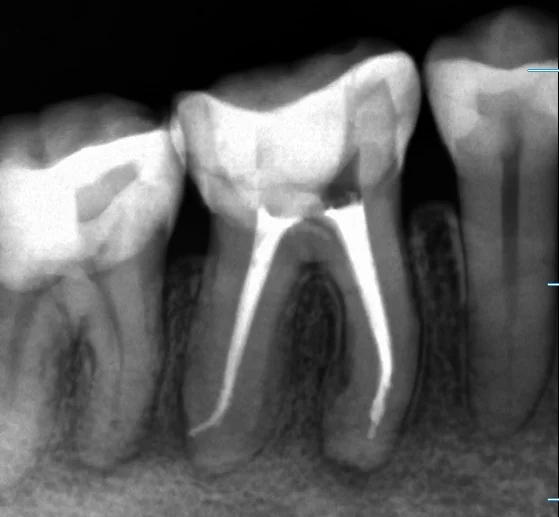

そして治療終了後の画像です

やはり根の先で大きく曲がっていました。

本来はこういう曲がっているところへのアプローチは難しいのですが、現在はそれを行いやすくする器具が非常に沢山出てきています。